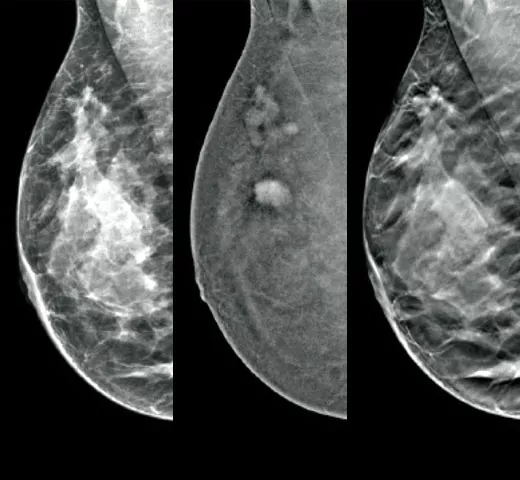

Cutting-Edge Imaging

Optimal cancer detection starts with high quality imaging. Integrate the EUREF-approved1 Hologic mammography technologies into your clinical pathway to maximise efficiency in your imaging workflow.

Confident Cancer Detection

The clinically proven tomosynthesis and contrast enhanced imaging technologies, plus future-proofed AI powered solutions at the point of care, help you make better clinical decisions while accelerating reading time and improving operational efficiency.

Reveal fine details with fast and high resolution 3D Mammography™ exam5 using our advanced detector and innovative 3D™ imaging technologies. These help to detect more invasive cancers with confidence6 With the integration of additional AI-powered solutions, this is a smart platform supporting breast cancer detection, workflow optimisation and risk assessment.

Clarity HD™ High Resolution Tomosynthesis

Producing high-resolution tomosynthesis images normally means slower read times. However, combining Clarity HD high-resolution 3D imaging with Genius AI Detection technology and 3DQuorum allows you to unleash fast and high resolution 3D images,5 accelerating screening and analysis.

Intelligent 2D™ Synthesised Imaging

For higher image quality, more detail, improved read times and low dose, this AI-powered software produces robust, yet natural looking, synthesised 2D images that are well correlated with the 3D mammography data. This enables radiologists to quickly and confidently see subtle mammography features and lesion morphology.

Genius AI™ Detection Technology